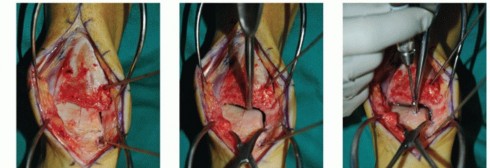

- TECH FIG 2 • A,B. Identifying the extent of the talar shoulder lesion. (continued)

Define the extent of the OLT (TECH FIG 2A,B).

Clinical inspection Review of CT scan

- TECH FIG 2 • (continued) C-E. Excision of the talar shoulder lesion using the microsagittal and oscillating saws. F. Talar shoulder lesion removed.

Excise the diseased portion of the talus (TECH FIG 2C-F).

Reciprocating and microsagittal saw (use cool saline to limit risk of heat necrosis) May need a small curette and rasp as well

Define the dimensions of the recipient site. Use a caliper and a ruler and double-check the measurements. - Harvesting Graft from Donor Talus